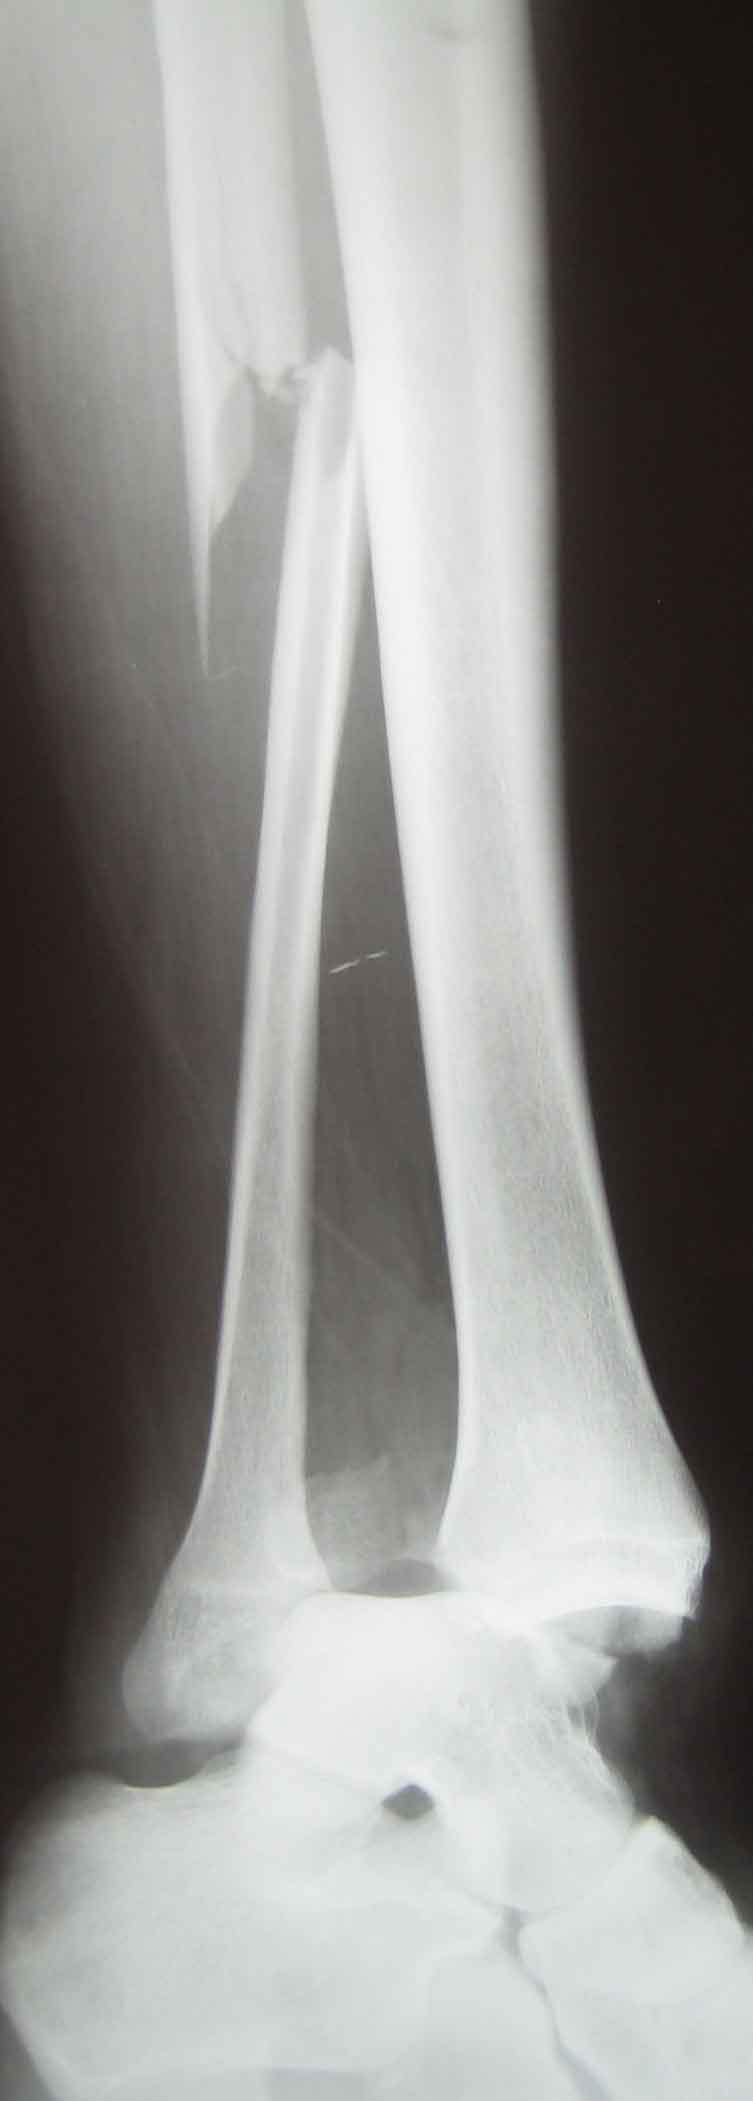

Вложение не в текстовом формате было извлечено…

Имя     : 14.jpg

Тип     : image/jpeg

Размер  : 47290 байтов

Описание: отсутствует

Url     : http://weborto.net:8080/pipermail/ortho/attachments/20101026/e044de93/attachment-0003.jpg